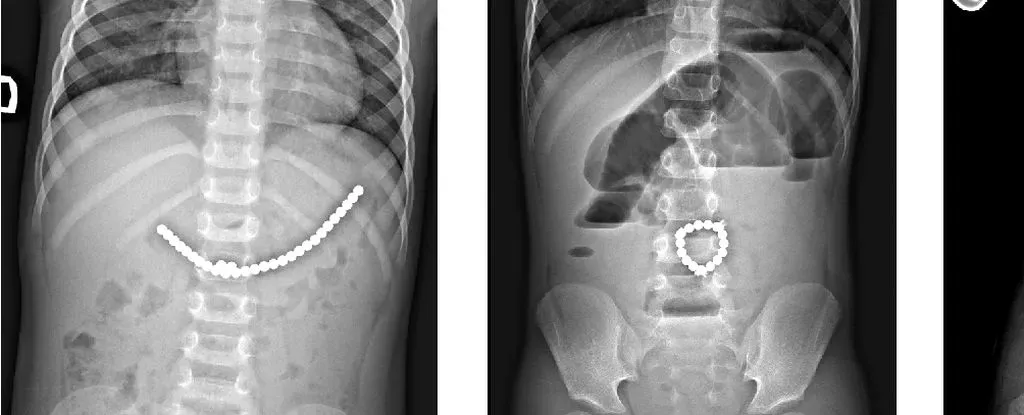

200 颗磁铁在患儿腹中形成了磁铁链。来源:Lekamalage et al.,?NZMJ, 2025

手术取出的磁铁链?来源:Lekamalage et al.,?NZMJ, 2025

儿童吞食小型磁珠后的 X 光片。来源:Da?kevi?iūt? et al.,2017